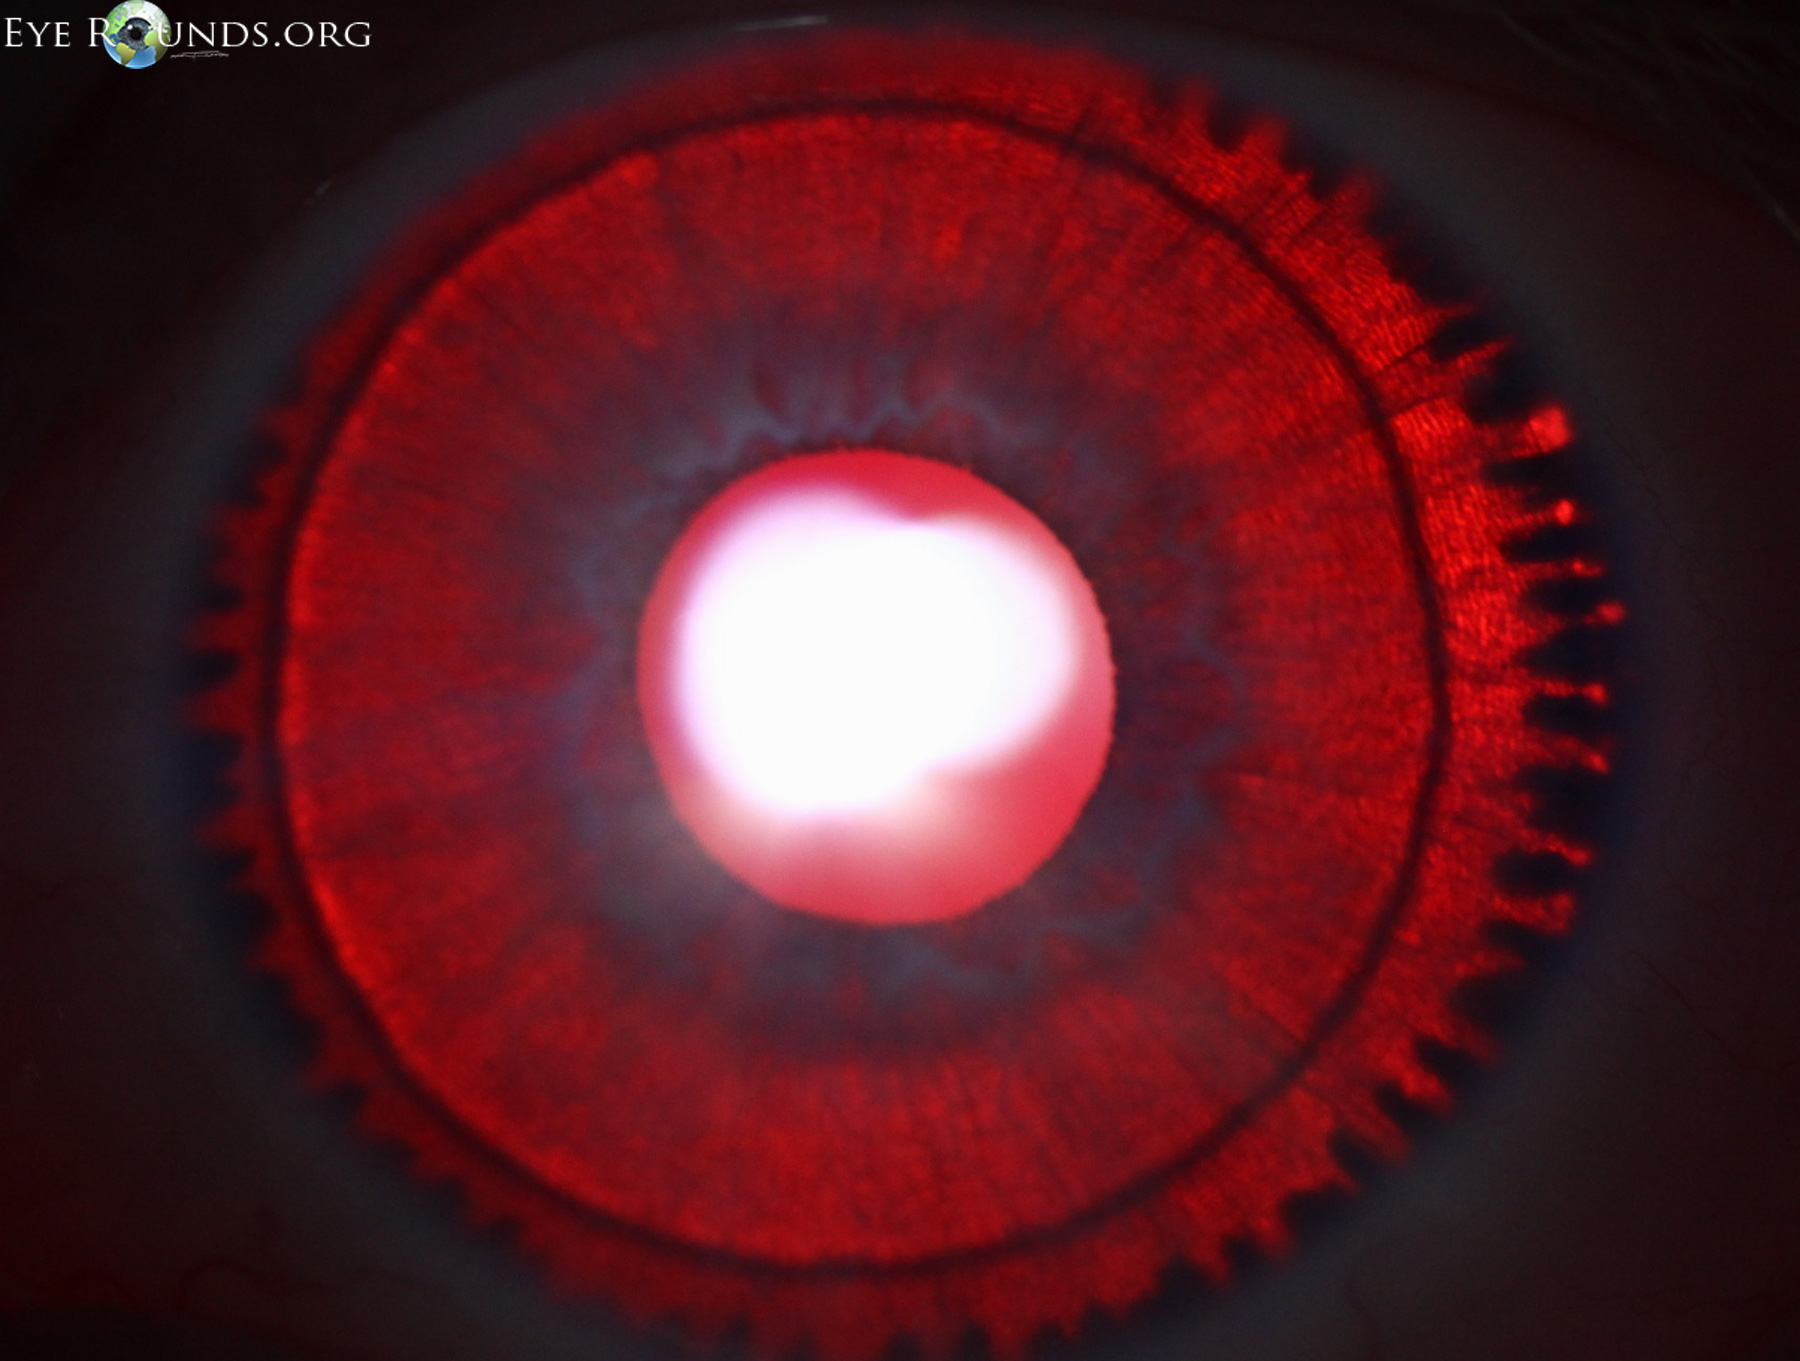

This 7-year-old girl presented with decreased vision and nystagmus and was diagnosed with oculocutaneous albinism (OCA).

OCA is typically inherited in an autosomal recessive fashion and is characterized by decreased melanin and subnormal vision since birth. Findings on exam include hypopigmentation of the skin, hair, and irides with diffuse iris transillumination defects on retroillumination, as seen in the photograph. Decreased acuity can be attributed to foveal hypoplasia which is apparent as an abnormally small or absent foveal depression as seen in this optical coherence tomography (OCT) render. Albinism can also be limited solely to the eyes in ocular albinism which most commonly has X-linked recessive inheritance.